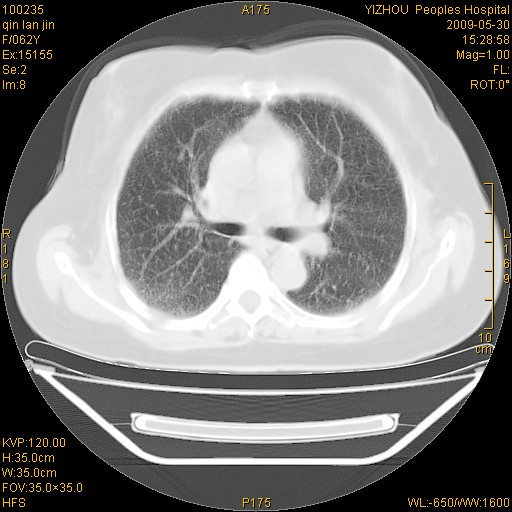

标题: CT20268:肺泡癌?间质性肺炎? [打印本页]

标题: CT20268:肺泡癌?间质性肺炎?

女,62岁,近二年经常咳嗽,近二个月,消瘦、乏力。

前面一张胸片是今天照的,后面一张胸片是去年9月份的。